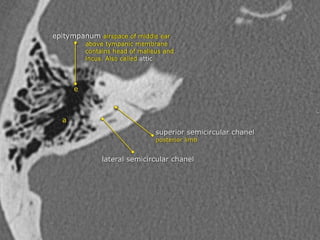

Middle Ear

 Epitympanum (attic):

Middle ear above line from

scutum tip to tympanic

 Mesotympanum: Middle

ear proper

 Hypotympanum: Shallow

trough in floor of ME

Three compartments in coronal plane.

• A line drawn from lower edge of the scutum to the tympanic

portion of the facial nerve -epi/mesotympanum.

• parallel to the floor of the external auditory canal

meso/hypotympanum

a) The Epitympanum :

• Communicates with the mastoid via the aditus ad antrum

• Normally, the mastoid is an air-filled cavity divided into

numerous compartments by mastoid septations

• The mastoid air-cell size and configuration are highly variable

• The mastoid air cells are traversed by the Koerner septum,

which is a thin bony structure formed by the petrosquamous

suture that extends posteriorly from the epitympanum,

separating the mastoid air cells into medial and lateral

compartments

The semicircular canals

 are components of the bony labyrinth within the

petrous temporal bone (PTB) along with the cochlea and vestibule.

They contain the semicircular ducts, part of the

membranous labyrinth which are responsible for kinetic balance.

 There are three semicircular canals on each side, each forming two

thirds of a full circle which are orientated perpendicular (at right

angles) to each other. They all open into the vestibule. They have

differing and variable lengths but uniform diameters of approximately

1 mm.

Lateral (horizontal) semicircular canal (LSCC)

orientated 30 degrees to the horizontal. shortest of the semicircular canals

hair cells of the lateral semicircular duct supplied by the superior division of CN

VIII.